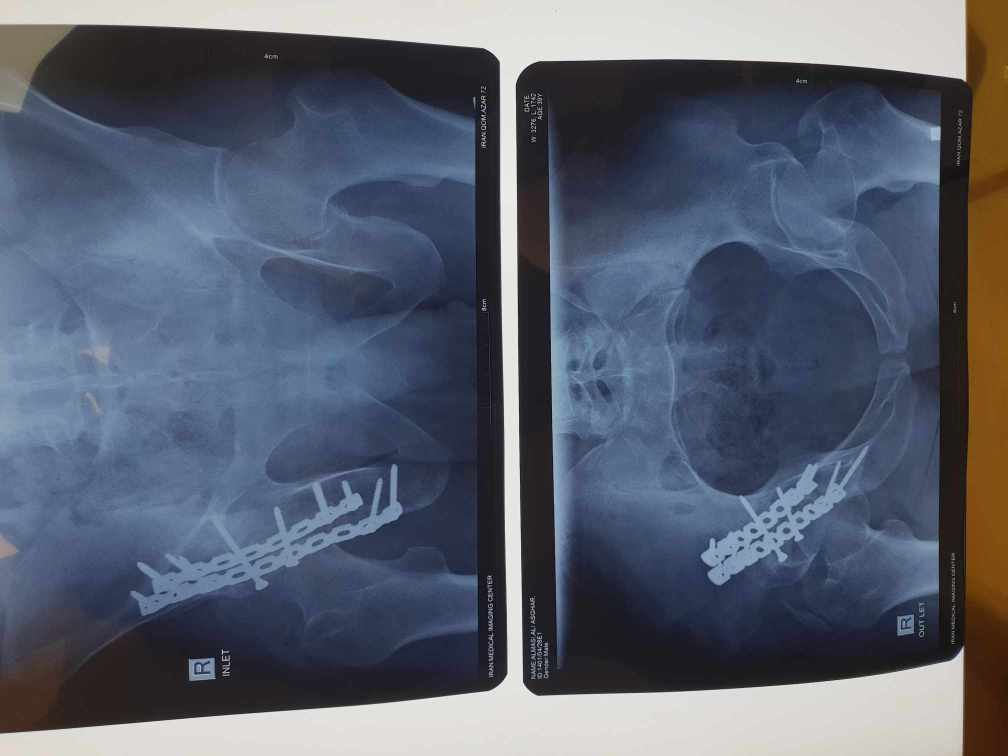

نمونه کارها

جراح و متخصص ارتوپدی